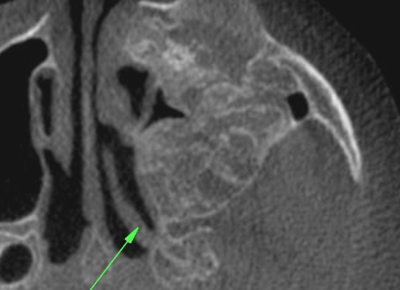

Consultation services for other doctors who utilize CBCT, CT or MRI scans in their patient care. Click on below images to download some sample reports.